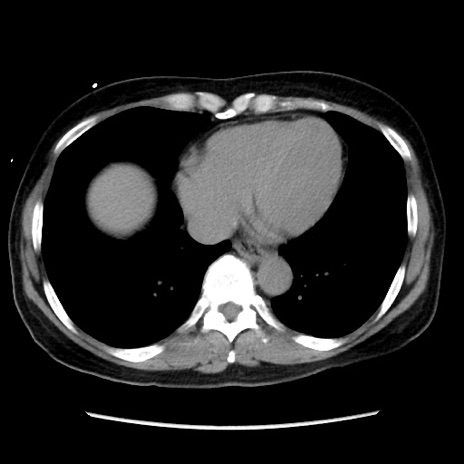

症例10(横断像)

【症例】 50歳代女性

【主訴】 腹痛

【現病歴】前日生レバーを食べた。今朝に排便あり。 昼前に突然発症の腹痛を生じ、当院救急外来を受診した。

【既往歴】 子宮筋腫にてで子宮全摘後

【身体所見】 意識清明、腹部:平坦、軟、下腹部やや左を中心に圧痛・反跳痛あり、筋性防御あり

【データ】WBC 7800、CRP 0.07